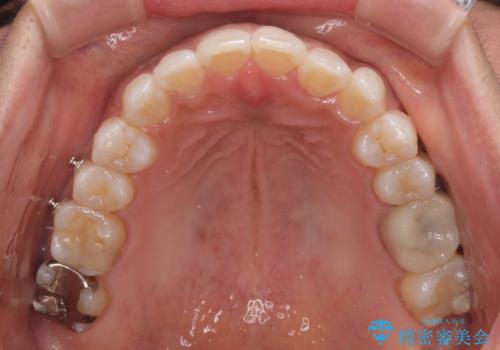

クロスバイトを治したい インビザラインによる矯正治療

- 前歯のクロスバイトを気にして来院された患者様です。

上下ともに、前歯部を中心にやや叢生が認められる程度であったため、ワイヤーでもインビザラインでも、どちらでも対応可能な状態でした。

咬合力が非常に強く、治療が進むにつれて上下奥歯が離開してくることが予想されるため、治療途中から上下の顎間ゴムを使用することを理解いただき、インビザラインによる矯正治療を行うこととしました。

咬合力による臼歯離開は顎間ゴムで改善されましたが、それとは別に下顎小臼歯がマウスピースに追従せず、補正のためのゴムかけが必要となりました。

大変なゴムかけ作業を頑張っていただき、無事に治療を終えることができました。